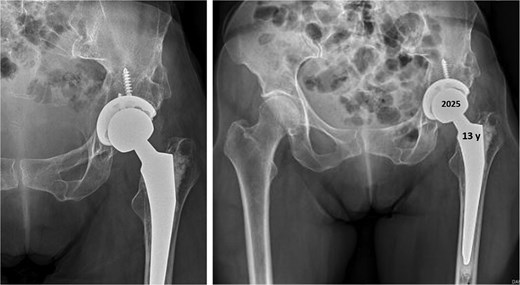

At 20-year follow-up, she presented with symptomatic hip pain. Pelvic radiographs (Fig. 2) showed signs of moderate osteoarthritis in the left hip (Tönnis Grade III). Radiographs showed signs of acetabular retroversion (ischial spine sign and posterior wall sign).

Postoperative radiographs of the pelvis 20 years after pelvic osteotomy, showing signs of moderate osteoarthritis in the left hip (Tönnis Grade III), and radiographic evidence of acetabular retroversion (ischial spine sign and posterior wall sign).